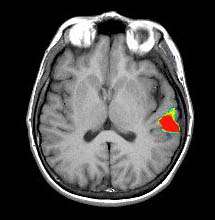

| Activación |

El hemisferio izquierdo muestra activación predominante. Se activaron las siguientes áreas: Área de Broca, porción posterior izquierda de las circunvoluciones temporales inferiores y medias (área 37 de Brodmann), parietal izquierdo y corteza premotora izquierda. Se observa una amplia activación en la cara inferior de los lóbulos occipitales. La activación principal en la derecha está ubicada en la cara inferior del lóbulo frontal (área 11 de Brodmann), un hallazgo observado constantemente en este paradigma. |